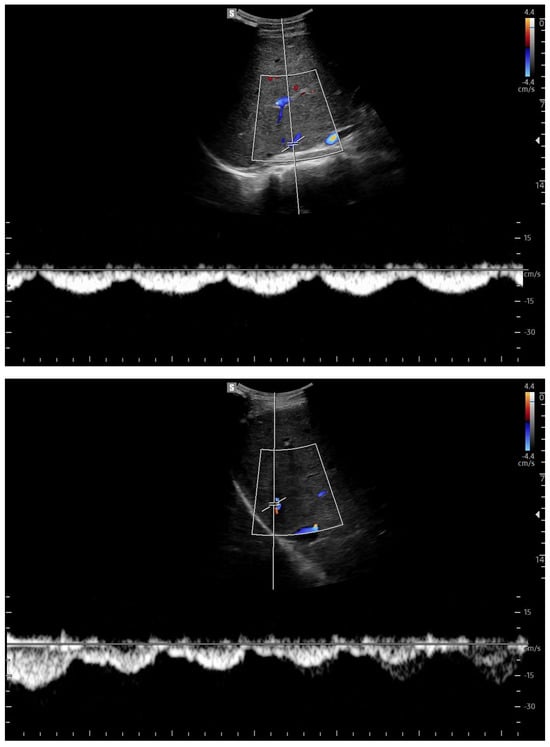

Doppler patterns in Fontan patients resemble those observed in chronic liver disease, including reduced portal flow velocity (mean flow velocity < 14 cm/s) [56]. The Fontan procedure inevitably alters hepatic venous waveforms on Doppler US (Figure 10, Figure 11, Figure 12 and Figure 13). Inverted portal flow has a specificity of 100% for diagnosing PHTN [57] (Figure 12). The hepatopetal phase pattern in the hepatic vein differs between patients with total cavo-pulmonary anastomosis (including both lateral tunnels and extracardiac conduits) and those with atrio–pulmonary connection [58,59,60]. In atrio–pulmonary connection, hepatopetal flow is preserved (Figure 10), reflecting the exclusion of atrial contribution to venous circulation, whereas in total cavo-pulmonary anastomosis, flow reversal (Figure 11) occurs only during early expiration. Similarly to congestive heart failure, hepatic veins and the IVC are dilated, with abnormally increased hepatic vein pulsatility, regardless of the anastomosis technique [54,61,62]. The loss of the normal three-phase Doppler pattern in hepatic veins is universal following bi-cavo-pulmonary surgery due to the absence of atrial contraction. The presence of a monophasic pattern indicates advanced liver injury [63].

Figure 10.

Doppler Ultrasound of the middle hepatic vein showing the loss of the normal three-phase pattern due to the absence of atrial contraction.

Figure 11.

Preserved hepatopetal portal flow in atrio–pulmonary connection.

Figure 12.

Inverted portal flow in cavo-pulmonary anastomosis.

Figure 13.

Changes in hepatic vascularization in a patient with FALD. The middle hepatic vein is patent, although irregular, within the context of the parenchymal nodularity.

Among individuals with Fontan physiology, the hepatic veins typically show a dampened, predominantly hepatopetal monophasic waveform, reflecting the presence of long-standing hepatic congestion. Venous flow velocities are markedly reduced compared with those measured in healthy individuals [63,64]. In contrast, in later stages characterized by cirrhosis and increased hepatic stiffness, further dampening or paradoxical changes in the venous flow pattern may be observed [37,56,64].

In particular, the hepatic venous Doppler waveform offers valuable insight into hemodynamic changes over time. In the early post-Fontan period, in the absence of atrial contraction and before structural liver damage is evident, the hepatic venous flow may display a relatively blunted monophasic or biphasic waveform with reduced phasicity, reflecting the lack of pulsatility and elevated central venous pressure [37,56,64].

As FALD progresses, and especially in the setting of developing cirrhosis, the Doppler waveform may become more dampened or even flat, corresponding to the increasing stiffness of the hepatic parenchyma, reduced compliance of the vascular bed, and worsening portal hypertension [37,56,64]. Simultaneously, the hepatic veins may appear dilated in the early and mid-stages of disease due to chronic venous congestion, but may show reduced caliber in later stages as fibrosis progresses and vascular remodeling occurs [37,56,64].